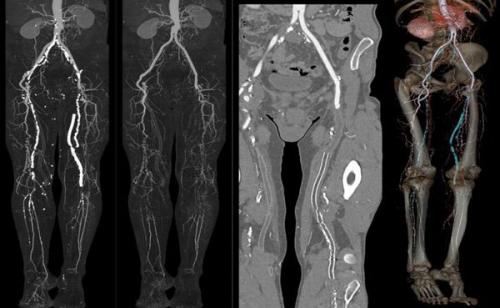

КТ-ангиография необходима для уточнения анатомии поражения и планирования операции. С этой целью внутривенно вводится контрастное вещество. Изображение моделируется из серии поперечных сканирований.